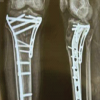

Case illustration 1: Depicted Fig. 2 shows the X-ray image of a patient who presented as type A of AO closed distal tibial fracture and comminuted distal fibula fracture with a tense swelling over ankle. He was managed primarily with open reduction and internal fixation with a plate for the fibula to maintain the length and proceeded with a hybrid external fixator for tibia. He was followed up for fracture union, and the hybrid external fixator was removed at 14-week postoperative period after complete union and ankle mobilization exercise were given. After an intensive physiotherapy session for ankle stiffness, the patient had achieved complete range of movements (Fig. 2). Case illustration 2: Patient presented with open fracture Gustilo Anderson type 3A, AO type C3 proximal tibial fracture with diabetes mellitus. He was operated with wound debridement and hybrid external fixator construct and followed up with serial X-rays, in which union occurred at 16-week postoperative period without any complications (Fig. 3). Case illustration 3: Patient presented with open Gustilo Anderson type 1, type A of AO classification of distal tibial fracture and displaced fibula fracture. He was operated with open reduction and internal fixation with plates for fibula fracture to maintain the leg length then a hybrid external fixator for the distal tibia. Union was achieved at 14-week postoperative period (Fig. 4).